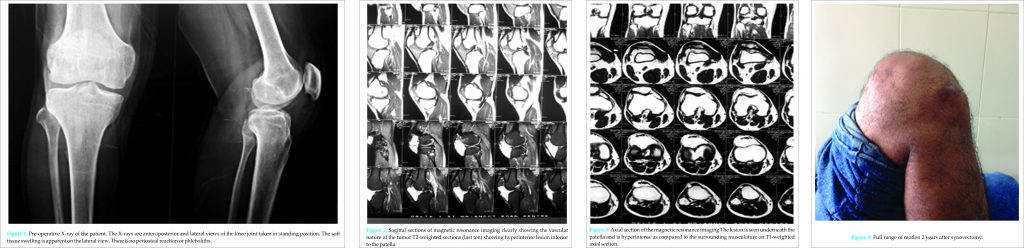

A 25-year-old Indian male presented with a history of pain and swelling in his right knee joint for 20 years for which he had received previous treatment in the form of simple analgesics only and had never reported to an Orthopedician. His physical examination revealed a soft, non-tender, palpable 3 cm × 3 cm mass on the lateral aspect of his right knee. In full flexion, the mass appeared more pronounced. It was compressible and filled back when the pressure was released. He denied any history of trauma, but there was a history of recurrent effusion in his knee. The patient had a near normal range of motion and no signs of instability. McMurray and Apley’s tests were negative. There was no difference in leg length, and there were no cutaneous lesions. Laboratory tests, including a complete coagulation profile, were all within normal range, and his medical, developmental, and family histories were unremarkable. Plain radiographs and magnetic resonance imaging (MRI) scans were obtained (Fig. 1, 2, and 3).

The plain radiographs showed no abnormality, but the MRI was suggestive of a vascular synovial tumor and the differentials kept were synovial hemangioma and synovial sarcoma. Diagnostic arthroscopy and incisional biopsy were done in the same sitting. The mass was excised completely, and synovectomy around the medial patella-femoral compartment was done in the same sitting (Fig. 4, 5). Some surrounding tissue showing bluish discoloration/inflammation was cauterized to prevent post-operative hemorrhage. The biopsy specimen was 4 cm in diameter, measuring synovial tissue. An intraoperative frozen section showed a hemangioma with huge, cavernous spaces but also containing capillary vessels. The final histological evaluation confirmed a cavernous synovial hemangioma (Fig. 6, 7, and 8). Post-operative period was uneventful with no recurrent effusion.